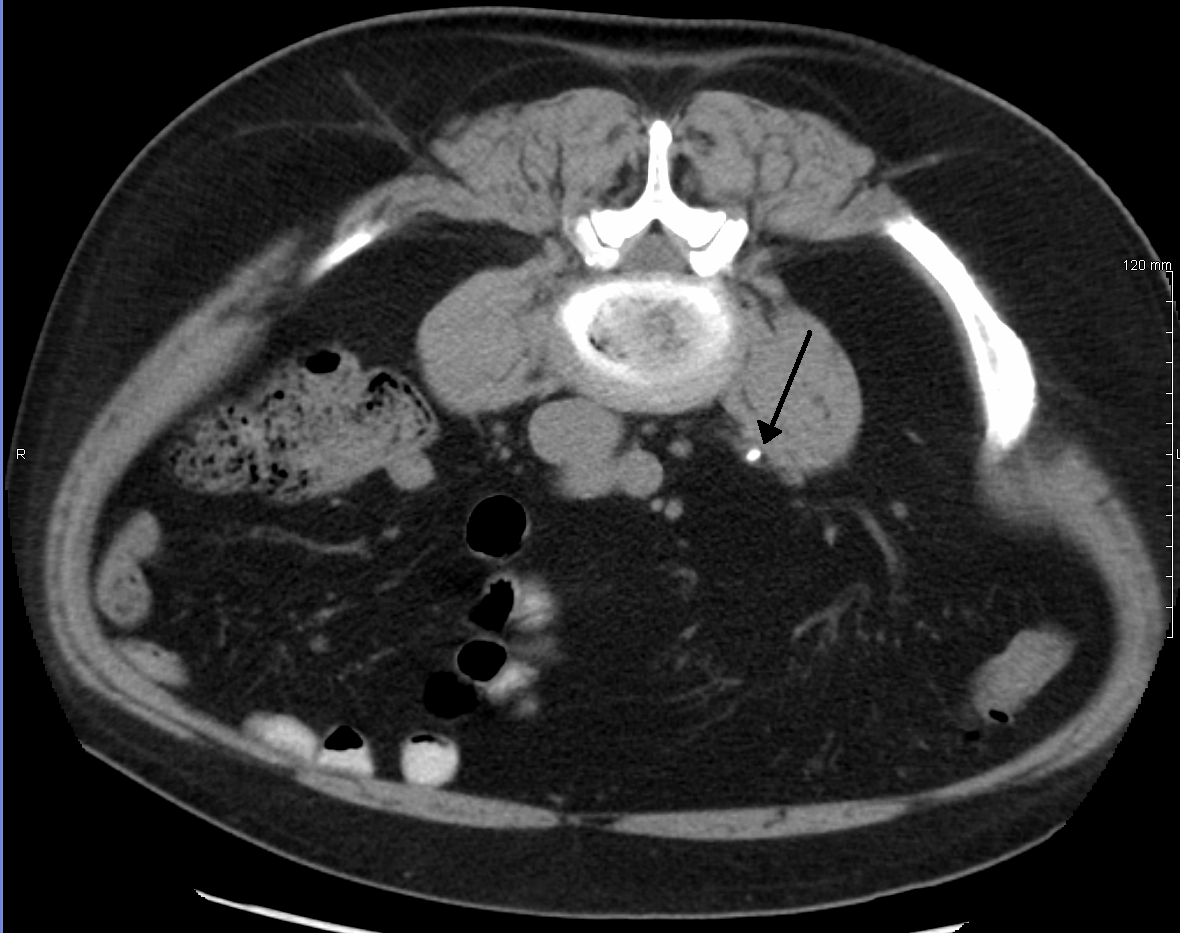

신장결석의 진단은 병력, 신체 검사, 요검사, 방사선학적 검사를 통해 얻은 정보를 바탕으로 이루어진다. 임상 진단은 일반적으로 통증의 위치와 심각도를 기반으로 이루어지는데, 이 통증은 전형적으로 산통성(간헐적으로 경련성 파동으로 나타남)이다. 결석이 신장을 막았을 때 허리 통증이 발생한다. 신체 검사에서는 발열과 병변이 있는 쪽의 늑골척추각 압통이 나타날 수 있다.

칼슘 함유 결석은 비교적 방사선 불투과성(X선에 불투과성)이 높아 복부를 포함한 전통적인 X선 촬영(특히 KUB 촬영)으로 종종 발견할 수 있다. KUB 촬영은 결석 형성자의 결석 크기 변화나 결석 통과 여부를 모니터링하는 데 유용하지만, 민감도가 낮기 때문에 급성기에는 유용하지 않을 수 있다.[34] 모든 신장 결석 중 약 60%가 방사선 불투과성이다. 일반적으로 인산칼슘 결석의 밀도가 가장 높고, 그 다음으로 수산칼슘 결석, 인산마그네슘암모늄 결석 순이다. 시스틴 결석은 약하게만 방사선 불투과성을 나타내고, 요산 결석은 일반적으로 완전히 방사선 투과성이다.

50세 미만이고 이전에 결석 병력이 있는 사람에게 결석 증상이 나타나지만 우려스러운 징후가 없는 경우 나선형 CT 스캔 영상은 필요하지 않다.[35] 또한 어린이에게는 일반적으로 컴퓨터 단층촬영(CT) 스캔이 권장되지 않는다.[36]

그 외의 경우에는 5mm 간격의 조영제를 사용하지 않는 나선형 CT 스캔이 신장 결석을 검출하고 신장 결석 질환 진단을 확인하는 데 사용하는 진단 방법이다.[2] 소변 속 특정 약물 잔류물(예: 인디나비르)로 구성된 결석을 제외하고는 거의 모든 결석이 CT 스캔에서 검출된다.